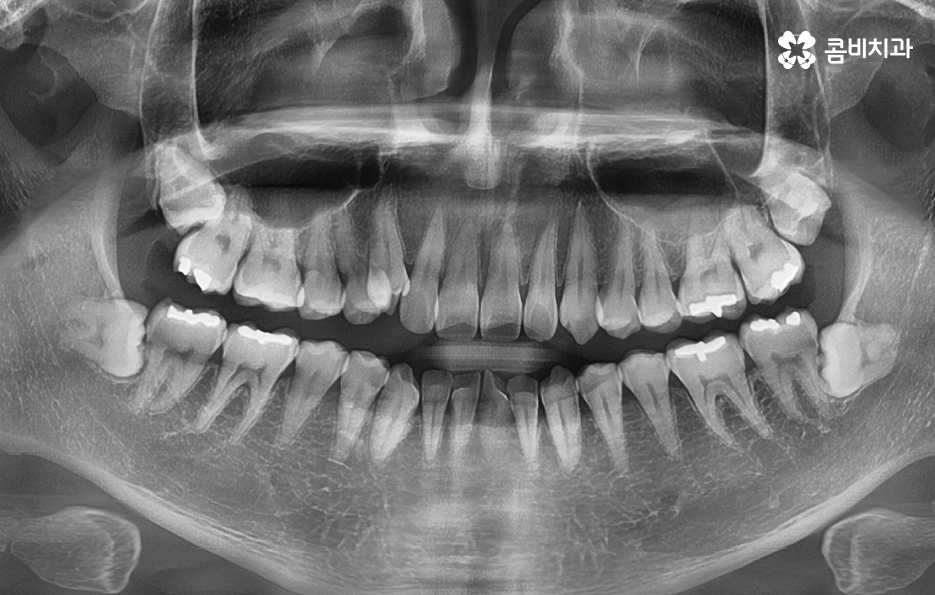

어금니는 사랑니와도 가깝고 나이가 들수록 충치 뿐 아니라 치아의 마모와 균열로 인해 다양한 이유로 손상될 수 있기 때문에 어금니 충치치료 뿐 아니라 파절로 인한 치료를 여러 번 받다보면 결국 인레이 치료를 받거나 신경치료 후 크라운을 씌워야 하는 경우가 많이 있는데요

위 사례에서 보시는 것처럼 어금니 씹는 면에 이미 과거에 보철이나 아말감으로 치료 했던 흔적이 많이 남아 있어요. 어금니는 저작 기능에서 주된 역할을 하기 때문에 치아의 씹는 면에서 충치가 발생하기도 하고 나이가 들수록 치아의 마모로 인한 깨짐이나 균열로 인해 고생하는 분들도 많을 거예요

저작 기능에서 주된 역할도 하지만 위 사진을 다시 보시면 사랑니가 부분 매복되어 있는 상태로 누워서 자라고 있기 때문에 사랑니와 어금니 인접면에서 청결 관리가 잘 안되는 문제로 충치나 치주질환을 앓고 계신 분들도 많기 때문에 사랑니로 인해 어금니 문제가 발생하는 경우도 많이 있어요

다시 위 어금니 사진을 살펴보면 사랑니가 매복되어 있긴 하지만 위쪽 부분이 살짝 잇몸 밖으로 드러나 있는 것을 볼 수 있는데요. 평소 칫솔질을 잘하더라도 사랑니로 인해 청결관리에 미흡한 점이 생기면 주변 치아에도 충치가 전염되는 등의 안좋은 영향을 주는 경우가 많으며 부분 매복 사랑니의 경우 충치가 아니더라도 잇몸 염증의 주된 원인이 되고 있기 때문에 발치하는 것을 각종 구강질환을 예방하기 위해 권하고 있어요

오늘 케이스 사진의 경우 사실상 사랑니 하나만 보더라도 주변 치아에 충치 및 치주질환을 일으키기 쉬운 사례이며 누운 사랑니로 인해서 어금니의 씹는면 만이 아니라 인접면 충치나 손상으로 이어지기 사례로도 볼 수 있는데요